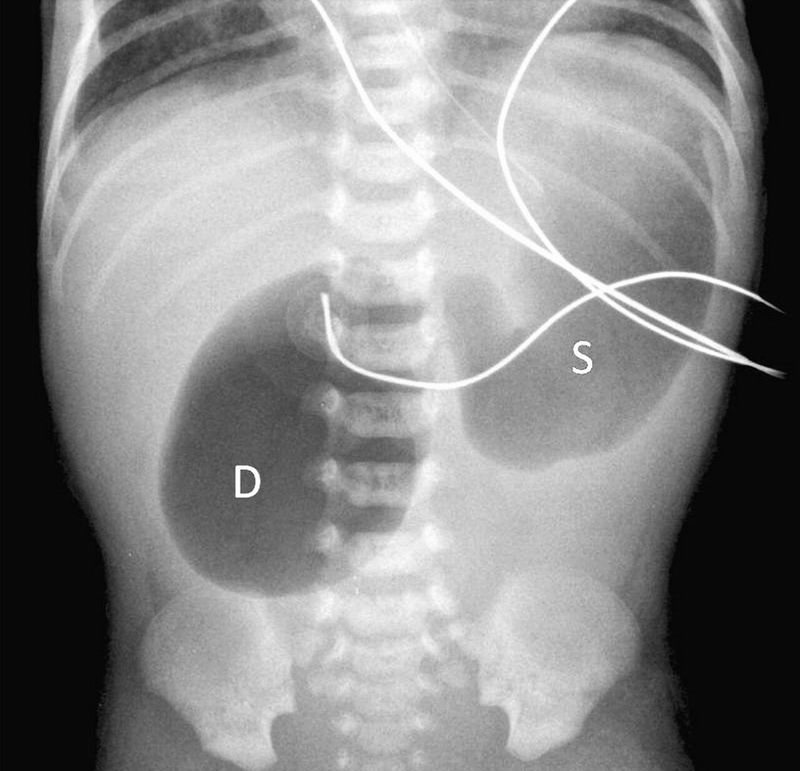

The Double Bubble Sign: This radiograph of the abdomen demonstrates a dilated stomach & an accompanying dilated proximal duodenum. There is no gas in the bowel distal to the dilated duodenum. This is called the "double bubble" sign and usually indicates the presence of duodenal atresia.